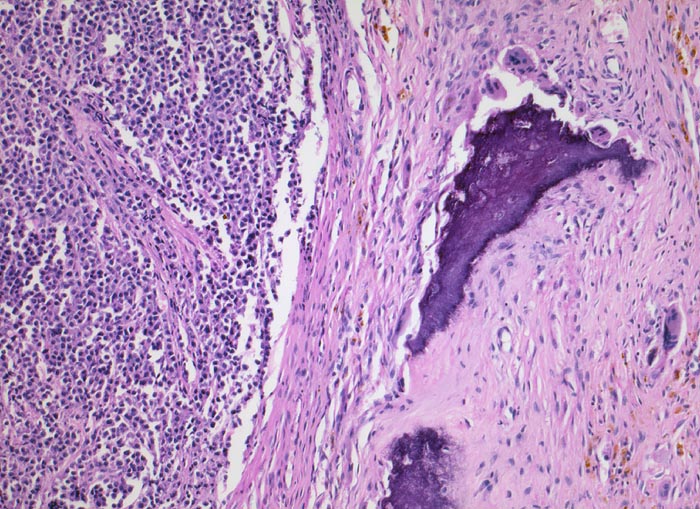

Morphologische Merkmale:

• Knochenmarkstanze mit nodulärer Hyperzellularität des blutbildenden Marks.

• Keine wesentliche Osteopenie.

• In den hyperzellulären Arealen dichte Rasen neoplastischer atypischer Plasmazellen.

• Ausserhalb der Plasmazellrasen findet sich spärlich residuelles blutbildendes Knochenmark.